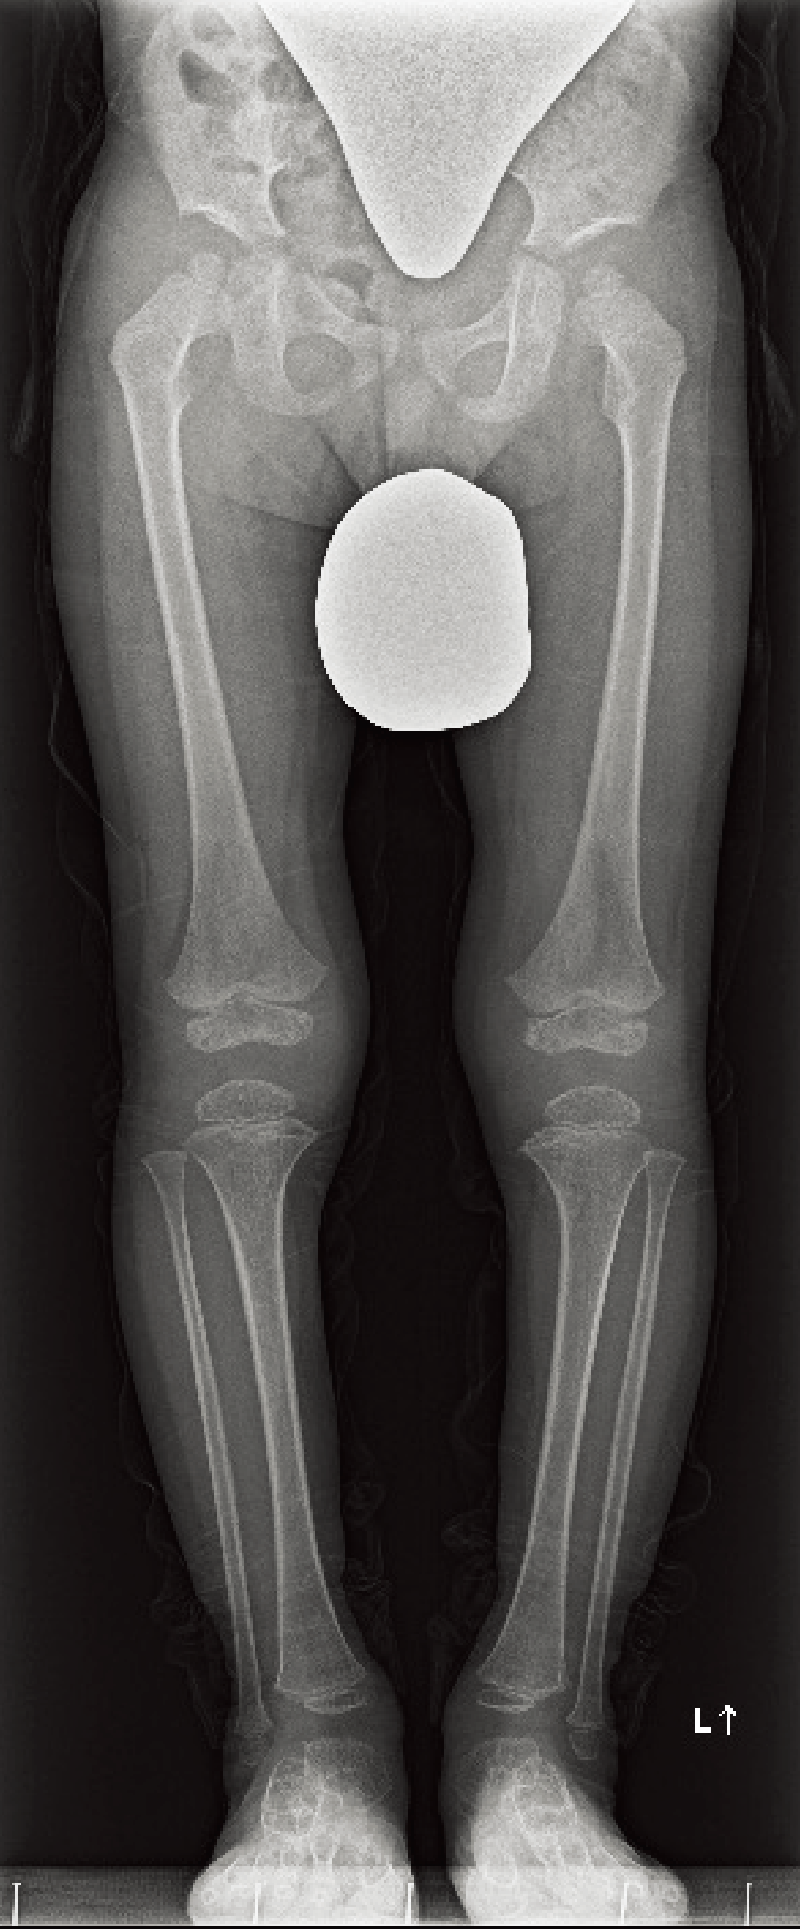

A. 背面像(6歳、女):内反膝を伴った体幹短縮型低身長。

B. 両下肢正面像(6歳、女):著明な内反膝および、大腿骨頭骨端核や膝周囲の骨端核の骨化遅延を認める。